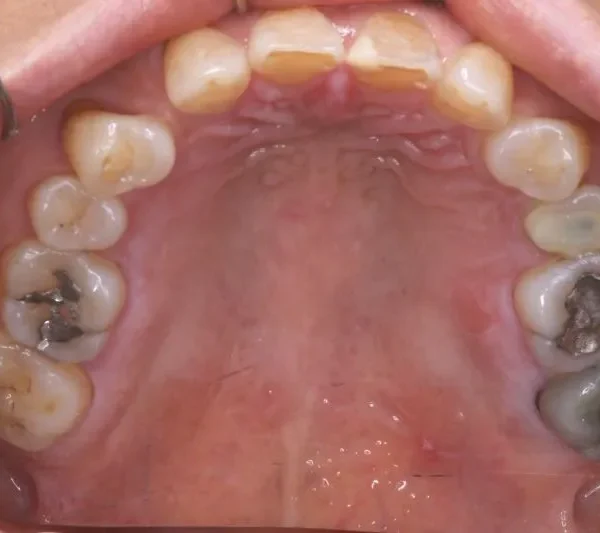

2.診断名あるいは主な症状 空隙歯列・先天性欠損歯

上の歯が2本足りないため上下のアーチが合わず、下の歯がガタガタになっています。

上下の幅をあわせ、噛み合わせから調整していきます。